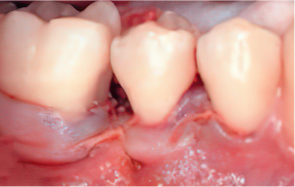

엠도게인 수술과정

-

STEP 01

잇몸을 절개

STEP 02

Scaling Root Planning을 실시

STEP 03

치석 및 치태 등 제거